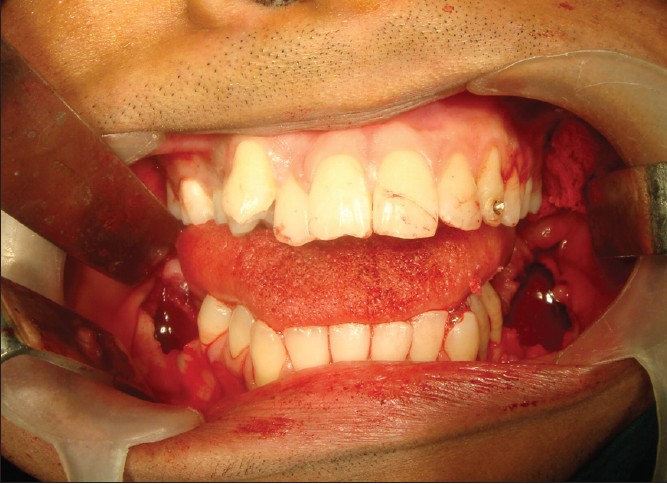

A 24-year-old male reported to the Department of Oral and Maxillofacial surgery in Mayya Multispecialty Hospital, Bangalore, India, complaining of asymptomatic facial swelling of 1 year. An intraoral clinical examination revealed a non-tender bilaterally palpable swelling. The swelling extended from the first premolar to third molar region on the right, and from the first premolar region to the retromolar trigone on the left [Figure 1] and [Figure 2]. The swelling obliterated the buccal vestibule bilaterally and there was associated mobility of the first and second molars on both sides of mandible. The overlying mucosa appeared normal in color, non-tender, hard in consistency, and smooth on palpation. The third molars were unerupted in all the four quadrants. There was no history of paresthesia in lower lip region. All the sensations were found to be normal in lower lip area on clinical evaluation. Vitality was found to be present in first and second molars, premolars, and anterior teeth after thermal stimulation test using hot gutta percha application on teeth. | Figure 1: Preoperative clinical photographs showing intraoral swellings in the retromolar area on right side

Click here to view |

| Figure 2: Preoperative clinical photographs showing intraoral swellings in the retromolar area on left side